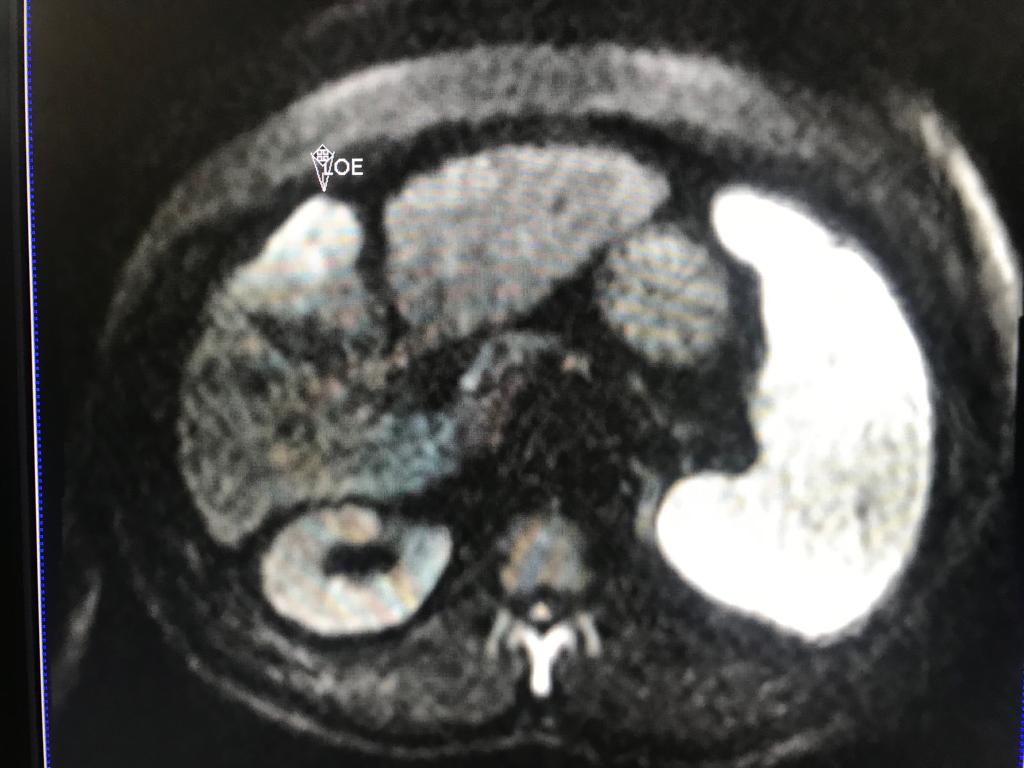

En el presente caso, encontramos una lesión típica de hepatocarcinoma en el segmento 5 ( hiperintensa en T2, restringe en la Difusión con ADC bajo. Realza heterogéneamente postcontraste EV, con wash out y presencia cápsula tardía).

El objetivo es identificar dentro de la multifocalidad de nódulos , un hepatocarcinoma precoz o de pequeño tamaño , cuando la posibilidad de tratamiento con intención curativa es viable , a pesar de la cirrosis.